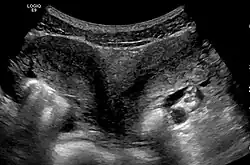

Uterus didelphys seen on ultrasonography

Besides a physical examination, the physician will need imaging techniques to determine the character of the malformation: gynecologic ultrasonography, pelvic MRI, or hysterosalpingography. A hysterosalpingogram is not considered as useful due to the inability of the technique to evaluate the exterior contour of the uterus and distinguish between a bicornuate and septate uterus. In addition, laparoscopy and/or hysteroscopy may be indicated. In some patients the vaginal development may be affected.